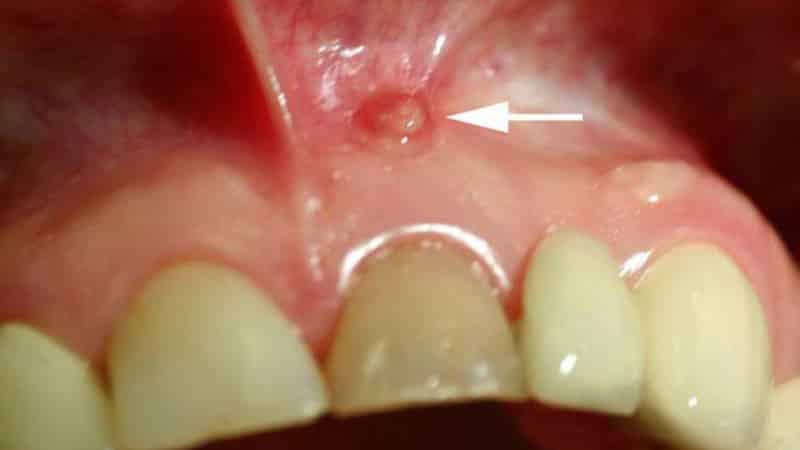

- появление фистулы с выделением гноя.

При периодонтите в области корня пораженного зуба образуется киста – это объемное образование, наполненное гноем, что приводит к отеку десны. Такой отек может проявляться периодически, исчезая и вновь появляясь.